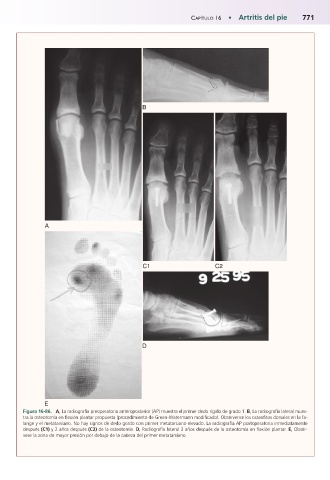

Figura 16-86.mA, La radiografía preoperatoria anteroposterior (AP) muestra el primer dedo rígido de grado 1. B, La radiografía lateral mues-

tra la osteotomía en flexión plantar propuesta (procedimiento de Green-Watermann modificado). Obsérvense los osteofitos dorsales en la fa-

lange y el metatarsiano. No hay signos de dedo gordo con primer metatarsiano elevado. La radiografía AP postoperatoria inmediatamente

después (C1) y 2 años después (C2) de la osteotomía. D, Radiografía lateral 3 años después de la osteotomía en flexión plantar. E, Obsér-

vese la zona de mayor presión por debajo de la cabeza del primer metatarsiano.